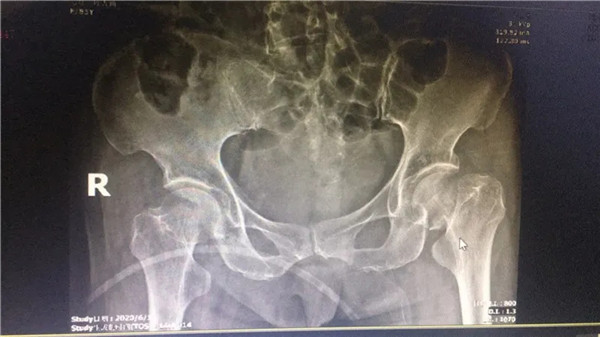

術(shù)前

經(jīng)拍片顯示,陳阿婆左側(cè)股骨頸骨折,須入院手術(shù)治療。一聽要手術(shù),家人便不禁擔(dān)憂起來,這么大年紀(jì)動手術(shù),身體吃得消嗎?危立軍副院長解釋道:高齡病人股骨頸骨折臥床,會導(dǎo)致一系列嚴(yán)重的并發(fā)癥,如疼痛,肺炎、血栓、泌尿系感染等等。隨便哪一項(xiàng)發(fā)生,對病人都是致命打擊,如果病人身體情況不是很差,還是建議進(jìn)行手術(shù),人工關(guān)節(jié)置換,能讓病人盡早恢復(fù)患肢活動,縮短臥床時(shí)間,降低死亡率及其他并發(fā)癥的發(fā)生幾率。在聽了危副院長的介紹后,家人遂即辦理了住院手續(xù)。